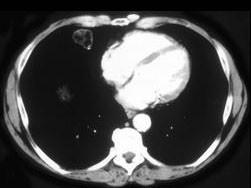

男,57岁,体检时发现肺部占位,CT检查如图,请选出最可能的诊断 ( )A、肺转移瘤B、肺曲菌病C、周围型肺癌D、肺结核E、肺错构瘤

问题 男,57岁,体检时发现肺部占位,CT检查如图,请选出最可能的诊断 ( )

选项 A、肺转移瘤 B、肺曲菌病 C、周围型肺癌 D、肺结核 E、肺错构瘤

答案 E